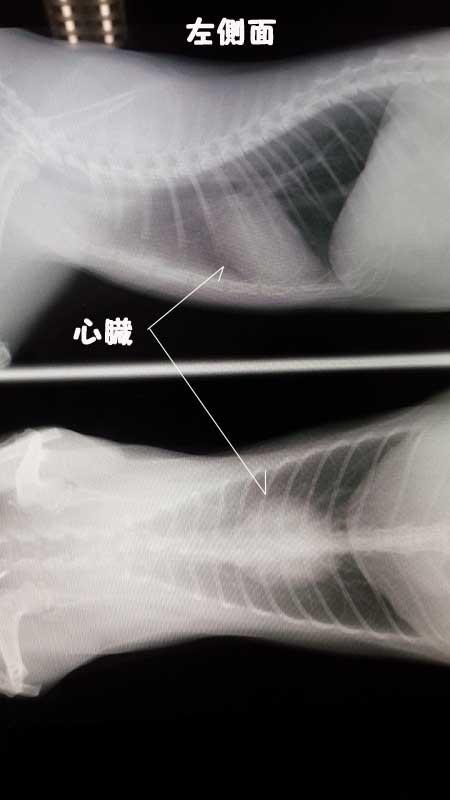

これが先日撮影したものです。

半年前と比べると体格も心臓も大きく成長してます。

左側にかすかに針のようなモノが見えますがICチップだそうです。